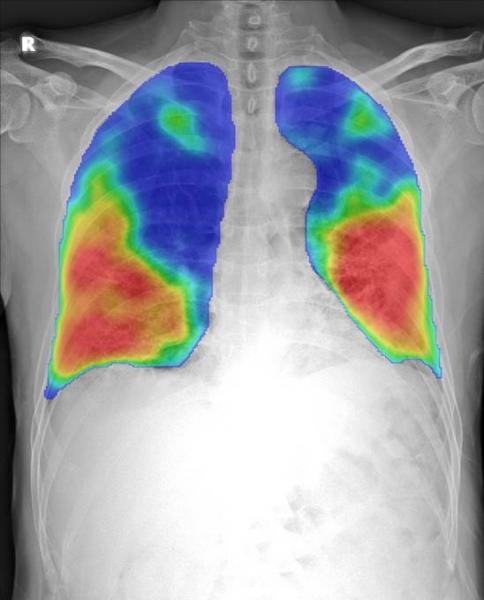

April 1, 2020 — Thirona and Delft Imaging launched CAD4COVID. This new artificial intelligence (AI) tool analyses X-ray images and is intended to support healthcare specialists manage COVID-19 cases. The companies have made the tool available free-of-charge in support of the crisis. Thirona and Delft Imaging are partnering with several hospitals and academic institutes worldwide to validate CAD4COVID.

Delft Imaging is specialised in tuberculosis (TB) screening and with its existing CAD4TB solution, which uses artificial intelligence to screen for TB. Over six million people have been screened in over 40 countries. Together with its sister company and AI-specialist Thirona, Delft Imaging developed a tool to help triage COVID-19 cases and indicate the affected lung tissue. CAD4COVID builds on the technical core of the CAD4TB software, developed and distributed by Thirona and Delft Imaging respectively. This software is used by Ministries of Health and tuberculosis-focused institutions, many of whom are now being tasked with helping to stop the spread of COVID-19 in their respective countries.

Preferred tools in the detection of COVID-19 are the RT-PCR test and the computed tomography (CT) scan, but in resource-constrained settings where the availability of such tools is limited and where COVID-19 is highly prevalent, X-ray can be a useful tool in the fight against COVID-19. In many countries, X-ray is currently used as a first-line triage before any further testing. Delft Imaging and Thirona have partnered with several academic institutes and hospitals in the Netherlands and abroad. These organisations will help with the development and validation of the software to support healthcare professionals in these times of crisis. The two Dutch companies aim to continuously improve the CAD4COVID software as more partners sign up.